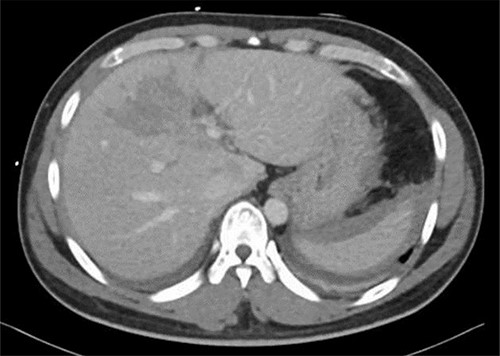

Resuscitation was carried on with 2 l of normal saline and two PRBC units to stabilize the patient. The computed tomography (CT) scan identified Grade 4 liver injury with hemoperitoneum (Fig. 2). Subsequently, the multiple bone fractures underwent surgical fixation, and post-operatively, he was hemodynamically stable. On the fifth day after admission, repeated CT scan demonstrated the liver injury with no evidence of hepatic pseudoaneurysm (Fig. 3). The patient remained stable with tolerated feeding with no abdominal pain or distension. On the Day 17, he developed abdominal pain mainly in the epigastrium, which was associated with nausea and deep epigastric tenderness. Abdominal ultrasound (US) (Fig. 4) and CT scan (Fig. 5) revealed complex, large intraparenchymal hepatic pseudoaneurysm (measuring about 58 × 41 × 30 mm) related to the left hepatic artery Segment 4 branch with surrounding hematoma located mainly at segment 4B/A ,and there was another tiny pseudoaneurysm seen at Segment 4A. Selective angiography confirmed the diagnosis of pseudoaneurysm with multiple blood supplies from Segment IV and Segment II.

Contrast-enhanced CT scan revealing a right hepatic artery pseudoaneurysm in the right lobe of the liver.